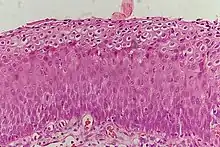

The earliest microscopic change corresponding to CIN is epithelial dysplasia, or surface lining, of the cervix, which is essentially undetectable by the woman. The majority of these changes occur at the squamocolumnar junction, or transformation zone, an area of unstable cervical epithelium that is prone to abnormal changes.[12] Cellular changes associated with HPV infection, such as koilocytes, are also commonly seen in CIN. While infection with HPV is needed for development of CIN, most women with HPV infection do not develop high-grade intraepithelial lesions or cancer. HPV is not alone enough causative.[13]

It most commonly occurs at the squamocolumnar junction of the cervix, a transitional area between the squamous epithelium of the vagina and the columnar epithelium of the endocervix.[12] It can also occur in vaginal walls and vulvar epithelium.

CIN is classified in grades:[17]

| Histology grade | Corresponding cytology | Description | Image |

|---|---|---|---|

| CIN 1 (Grade I) | Low-grade squamous intraepithelial lesion (LSIL) |

|

![]() |

| CIN 2/3 | High-grade squamous intraepithelial lesion (HSIL) |

| CIN 2 (Grade II) |

![]() | |

| CIN 3 (Grade III) |